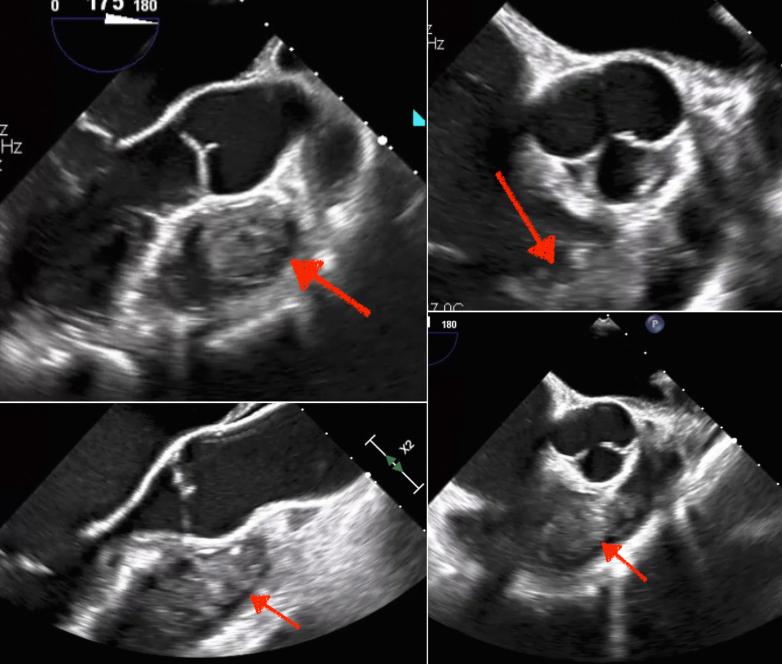

This case report describes the management of a 30-year-old male patient with a history of an advanced nonseminomatous germ cell tumor, hip fracture complicated by extensive deep vein thrombosis and pulmonary embolism, and on apixaban presenting with asymptomatic intracardiac teratoma and abdominopelvic metastases. Multidisciplinary intervention, including successful surgical excision of the intracardiac mass, highlights the importance of coordinated care and vigilant follow-up in optimizing patient outcomes and preventing life-threatening complications.

本病例报告描述了一名30岁男性患者的治疗情况,该患者有晚期非精原细胞瘤性生殖细胞肿瘤病史,髋部骨折并发广泛深静脉血栓形成和肺栓塞,正在服用阿哌沙班,现出现无症状心脏畸胎瘤和腹盆腔转移。多学科干预,包括成功手术切除心脏肿块,凸显了协调护理和密切随访在优化患者预后及预防危及生命并发症方面的重要性。